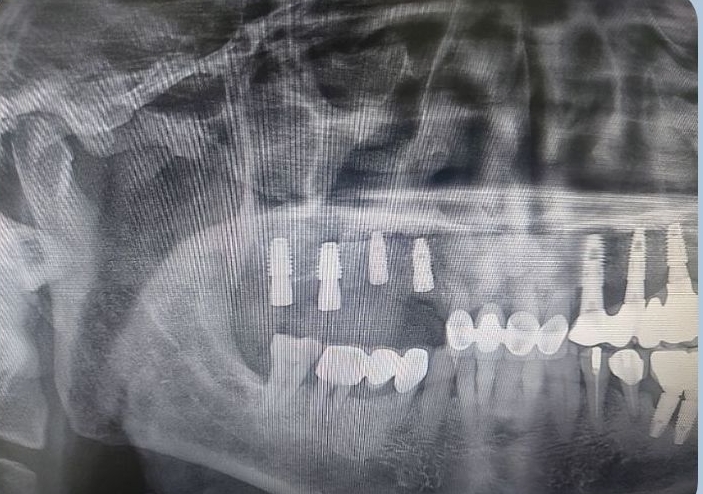

수술전 씨티와 구강스캐너를 이용하여

미리 모의 수술을 진행한 스텐트를 가지고 임플란트를 식립하는 네비게이션 임플란트 입니다.

이미 컴퓨터 상에서 수술이 끝난 결과로 재현한

스텐트를 가지고 수술하기에 잇몸절개가 필요없고

오후 4시 30 분에 시작된 수술은 5시경 끝이났고

환자분도 수술 후 아프지 않으셨다고 말씀하셨습니다.

10일 정도 후에 시행할 8개 식립 후 즉시부하

케이스에서 더 자세히 리뷰 하도록 하겠습니다.